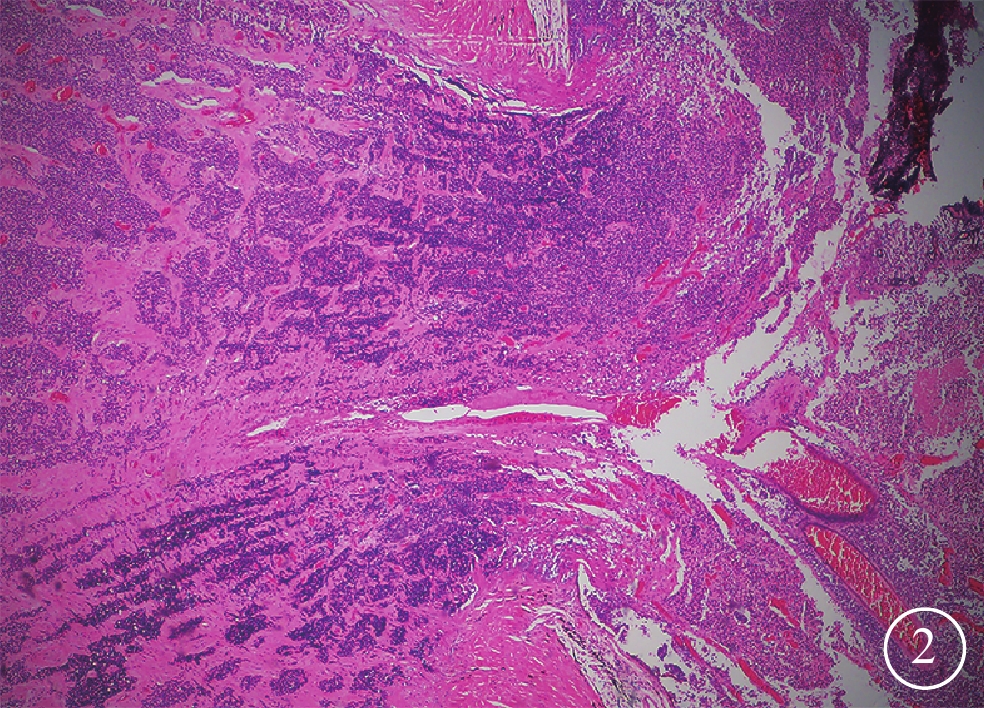

將患兒收入院行右眼眼球摘除手術。冰凍切片病理檢查,患眼腫瘤組織廣泛變性、壞死和鈣化,侵犯并穿透篩板9 mm(圖2);免疫組織化學染色觀察發現,膠質纖維酸性蛋白(部分+),Ki67(病灶70%+),增生細胞核抗原(+),Survinin(散在+),VIM(部分+),SYN(+),CD56(+),INI-1(+);視神經斷端未見腫瘤。手術后建議患兒接受預防性化學藥物治療(以下簡稱為化療),但其家屬因擔心化療后不良反應而拒絕;故手術治療后,每3個月定期隨訪,觀察患兒手術眼眼眶MRI及對側眼眼底情況。一直隨訪至手術后9個月,未見患兒腫瘤復發或全身轉移,對側眼未見明顯異常。獲得患兒家屬知情同意后,抽取患兒及其父母5 ml靜脈血送至基因檢測公司(北京邁基諾醫學檢驗所)行二代測序基因檢測。全外顯子基因檢測結果顯示,患兒存在ATP7B基因位點純合突變:chr13:52532469(NM_00053;exon8),c.2333G>T(p.R778L)(圖3)。該突變在正常人中的頻率為0.011 4,3種生物信息學軟件SIFT、PolyPhen_2、REVEL均預測該基因突變為有害。患兒父親該基因位點無變異。患兒母親該基因位點有雜合變異:chr13:52532469 (NM_00053;exon8), c.2333G>T, p.R778L,初步判定為致病性變異。全基因組基因拷貝數變異檢查發現,患兒基因13q13.1-q21.1片段(chr13:33561561-59357251)缺失(圖4),其中包括RB1、ATP7B等多個基因,目前染色體多態性數據庫不覆蓋該區域,Decipher致病數據庫中未報道過該基因突變,dbvar病例數據庫已有該基因區域缺失的病例報道;患兒父母該基因位點變異檢測結果為陰性,初步判定為疑似致病性變異。

RB的治療方法目前主要包括冷凍、激光光凝、玻璃體腔化療、靜脈化療、眼動脈介入化療和眼球摘除等,其目的是在保證患者生命的前提下保存眼球和視功能[6]。本例患兒首診時已處于RB晚期,影像學檢查顯示患眼視盤近端受累,符合眼球摘除的手術指征。手術后病理檢查顯示其腫瘤已侵犯并穿透篩板,具有組織病理學高危因素,原則上應予以預防性化療,以預防復發或病灶全身轉移。但由于家屬不能接受化療后不良反應,遂每3個月定期隨訪患兒手術眼MRI和對側眼眼底情況,至手術后9個月,未見腫瘤復發或全身轉移,對側眼也未見明顯異常。